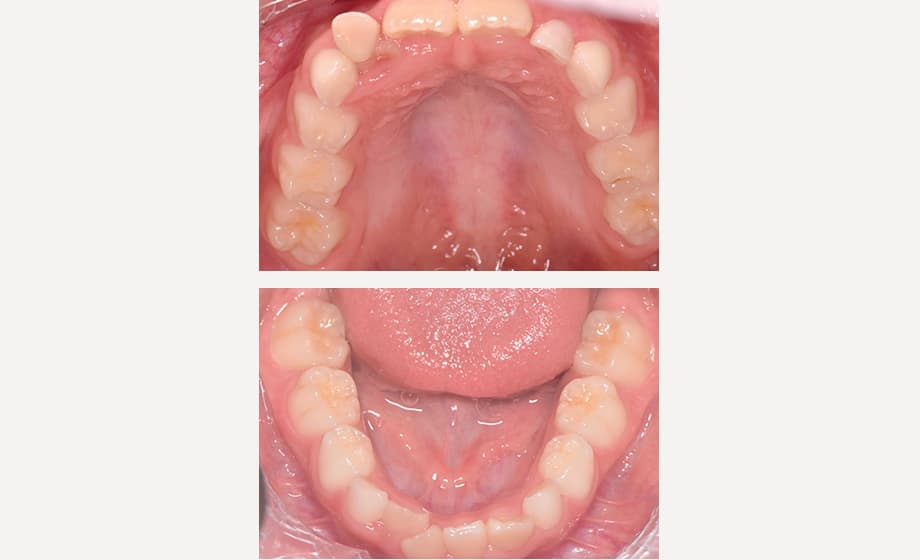

小児矯正では、お子さんの年齢や歯が生える状態によって乳歯列期、混合歯列期(Ⅰ期治療)、永久歯列期(Ⅱ期治療)に分けられます。

小児矯正では、あごの成長力を活かして歯の並ぶスペースを広げるように治療を進めます。そのため、スペース不足を補うための抜歯をしなくても済む可能性が高くなります。

小児矯正では、あごを広げる治療やお口まわりのクセの改善を通じて、歯並びが乱れる根本的な原因にアプローチします。そのため、治療後に歯並びが後戻りしにくいという特徴があります。